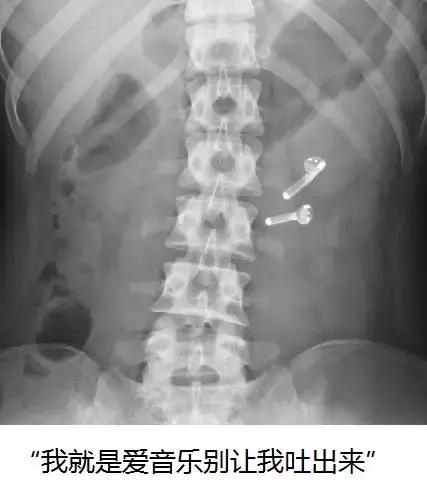

- 4.吞食异物

这也是比较常见的便血诱因之一。很多狗狗会出于好奇误食瓶盖、鱼线、玩具等异物,也有一些主人喜欢在自己做饭的时候喂狗狗几块骨头。这些东西很可能在消化过程中划伤狗狗的肠道黏膜,从而引发溃疡和便血。有些时候异物还会堵塞肠道,甚至诱发肠套叠,这个时候就只有手术才能解决了。